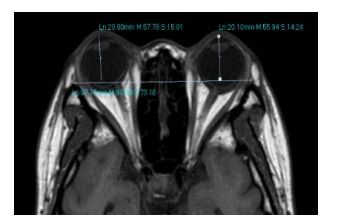

在T1WI序列视神经轴层面,以双侧角膜前缘与双侧颧弓连线的垂直距离即为眼球突出值(图 2)。

|

图 2 在T1WI序列测量眼球突出度 Figure 2 Degree of exophthalmus measured in T1WI sequence. |